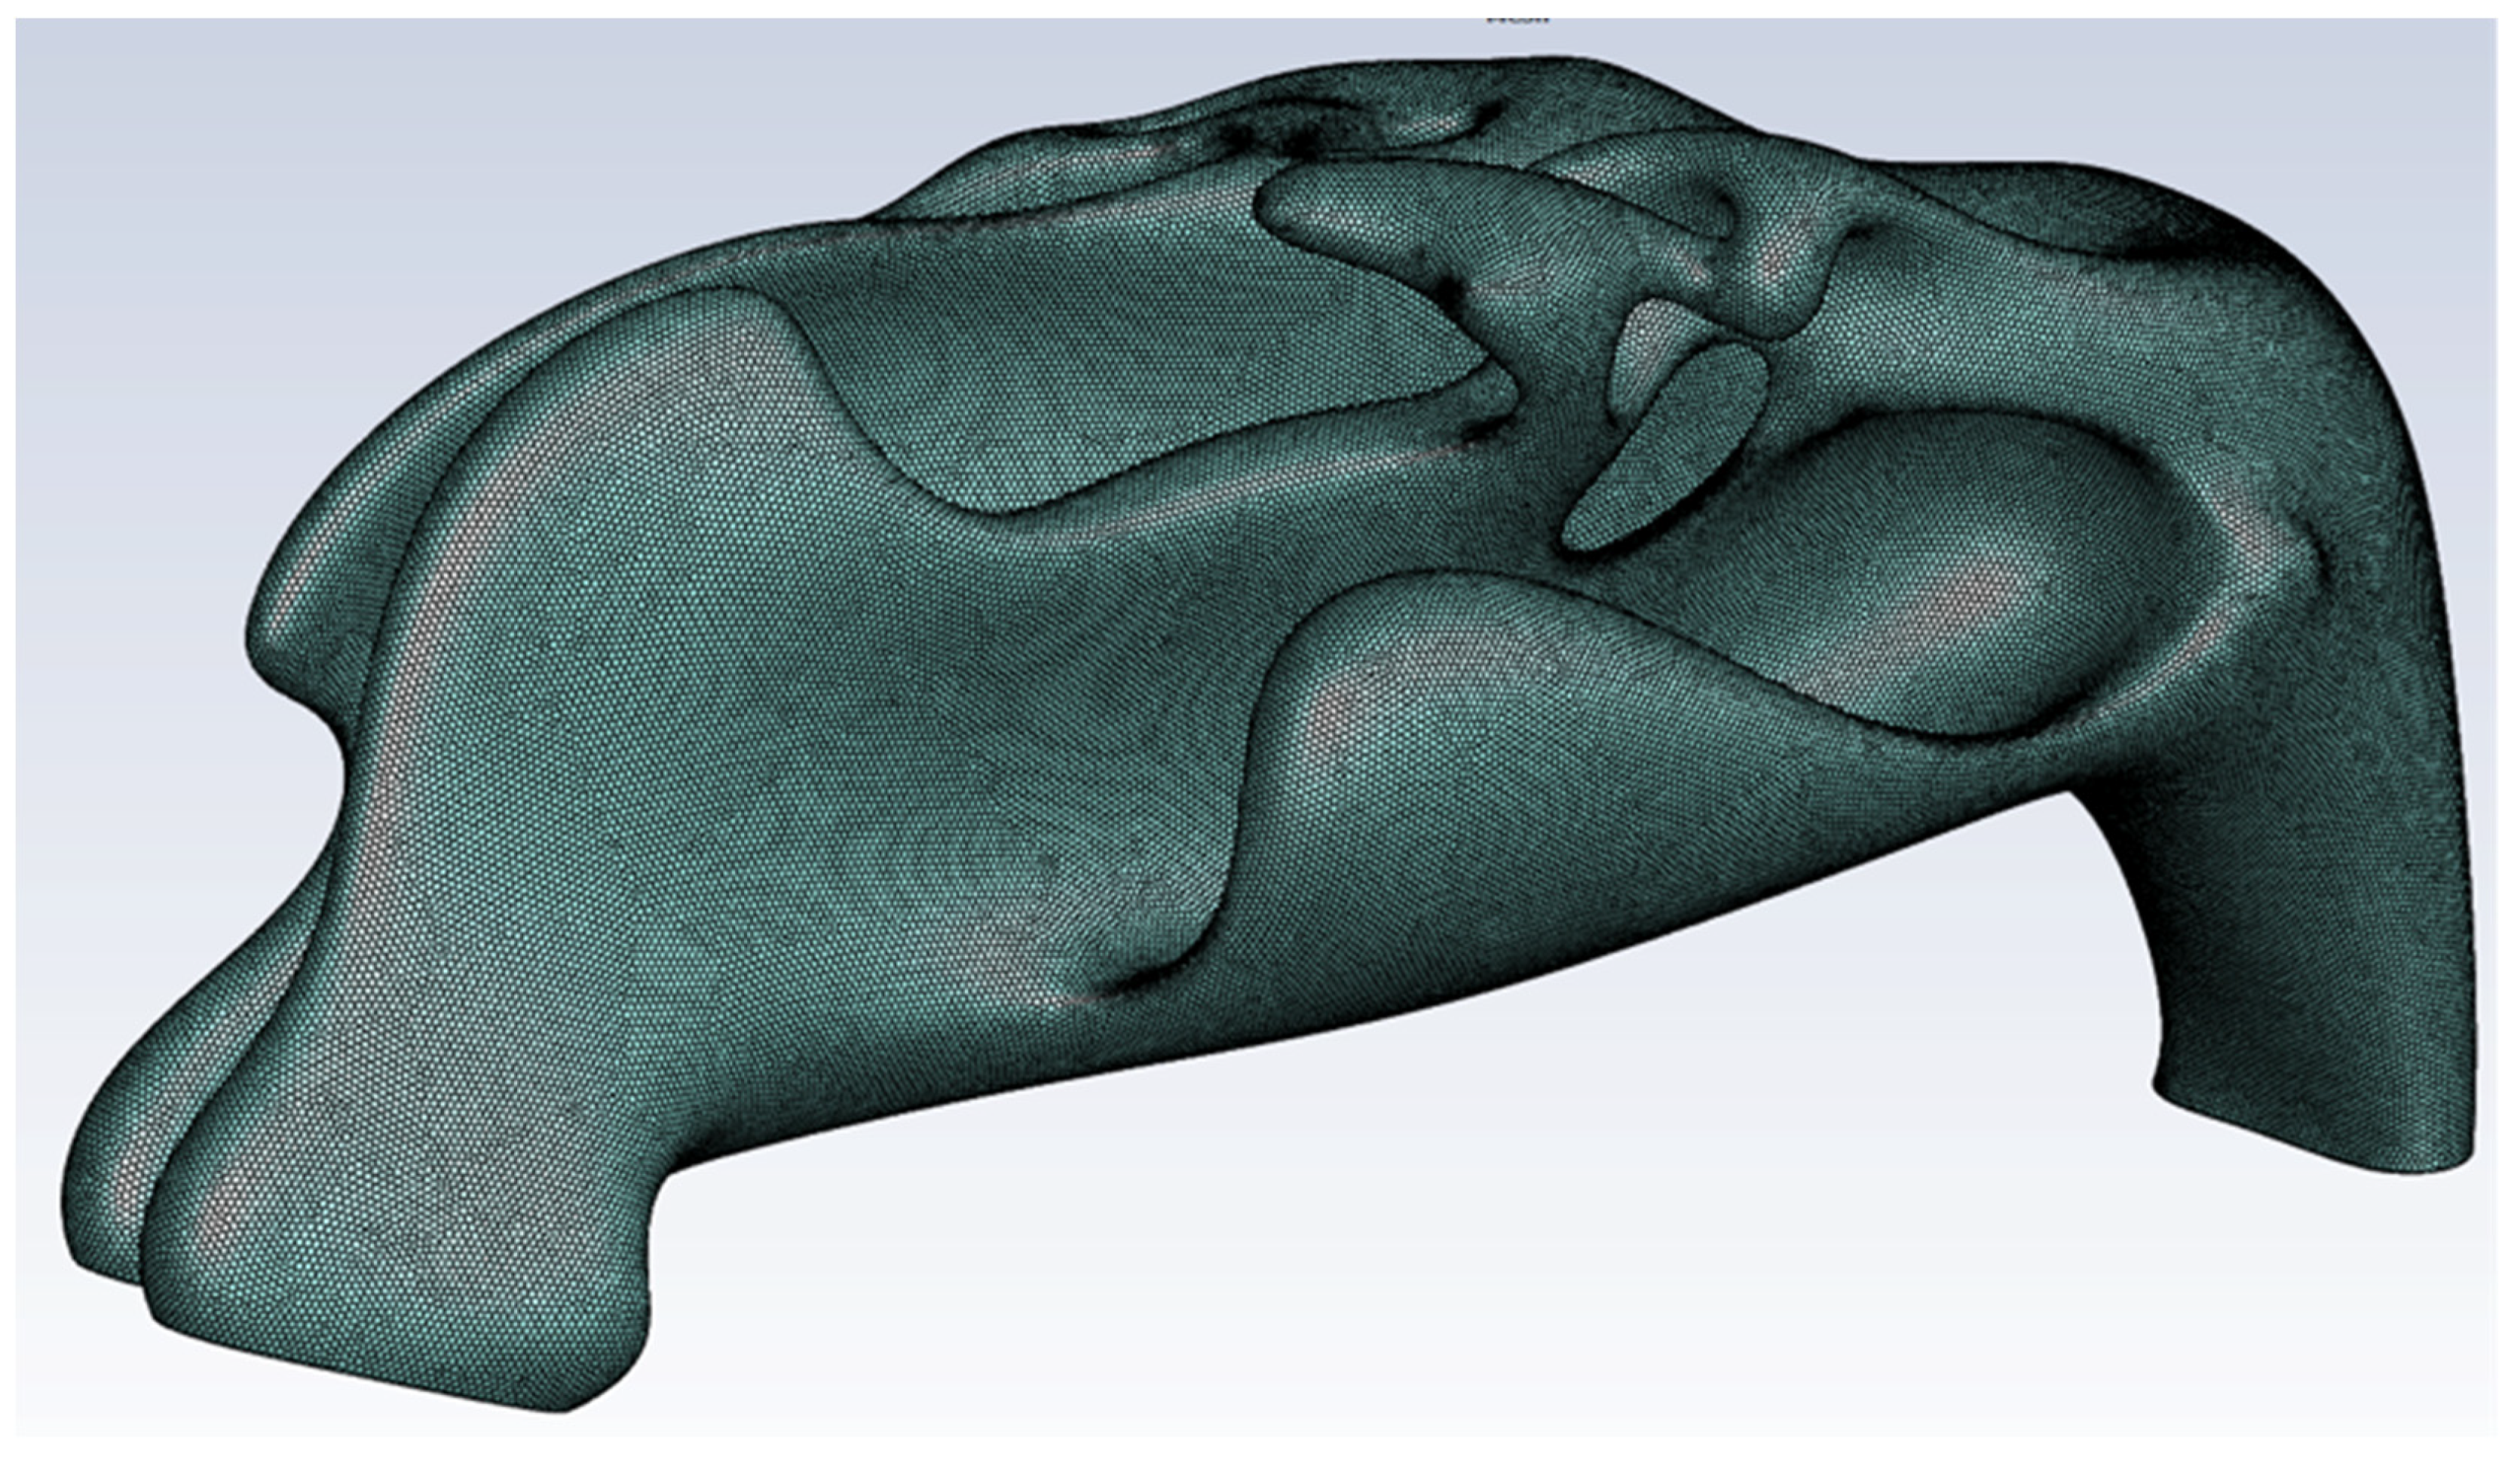

2.1. Virtual Model of the Nasal Cavity